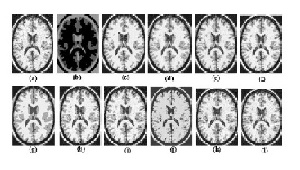

ام آر آی یکی از مهمترین روشهای تصویربرداری پزشکی است و قطعه بندی مرحله مهمی در بررسی تصاویر است.FCM رایج ترین روش برای قطعه بندی تصاویر کاربردی پزشکی است چون ماهیت فازی دارد. طوریکه یک پیکسل میتواند شامل چند دسته باشد و باعث می شود کارایی بهتری نسبت به روشهای crisp داشته باشد.اف سی ام مرسوم برای انجام خوب نشان دادن نویز و غیریکنواختی چگالی در تصاویر ام آر آی به شکست میخورد.انواع مختلف اف سی ام مانند BCFCM, PFCM, SFCM, FLICM, MDFCM, FCM−S1, FCM−S2, TEFCM, RFCMK, WIPFCM و KWFLICM برای غلبه بر این مشکل با استفاده از آمارهای مکانی موجود در عکس پیشنهاد شده اند.در این مقاله همه این تکنیک های استفاده شده برای قطعه بندی پیاد سازی شده اند و از نظر دو دوسته از توابع اعتبارسنجی،پارتیشن بندی فازی و ساختار ویژگی بر اساس کارایی آنها برای تصاویر ام آر آی نویز دار مقایسه شده اند.همه این اف سی ام های متنوع از نظر ضریب پارتیشن بندی،بی نضمی پارتیشن،پیچیدگی زمانی و دقت قطعه بندی تحلیل شده اند./1012/